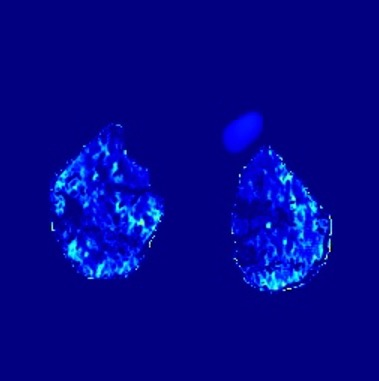

In the field of medical imaging, particularly in tasks related to early disease detection and prognosis, understanding the reasoning behind AI model predictions is imperative for assessing their reliability. Conventional explanation methods encounter challenges in identifying decisive features in medical image classifications, especially when discriminative features are subtle or not immediately evident. To address this limitation, we propose an agent model capable of generating counterfactual images that prompt different decisions when plugged into a black box model. By employing this agent model, we can uncover influential image patterns that impact the black model's final predictions. Through our methodology, we efficiently identify features that influence decisions of the deep black box. We validated our approach in the rigorous domain of medical prognosis tasks, showcasing its efficacy and potential to enhance the reliability of deep learning models in medical image classification compared to existing interpretation methods. The code will be publicly available at https://github.com/ayanglab/DiffExplainer.